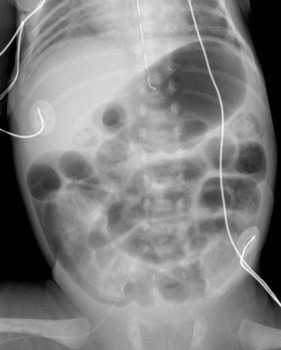

A

definitive radiographic finding is pneumatosis, gas in the bowel wall.

There is a "frothy" or "soap-bubble" bowel gas pattern. Linear or cresent shaped gas collections in the bowel wall may also be seen.

Another sign is unchanged bowel gas pattern over several films indicating

an ileus. More worrisome signs include gas in portal venous system and ascites.

| Multiple dilated loops of bowel with pneumatosis. | Extensive pneumatosis throughout the abdomen. |